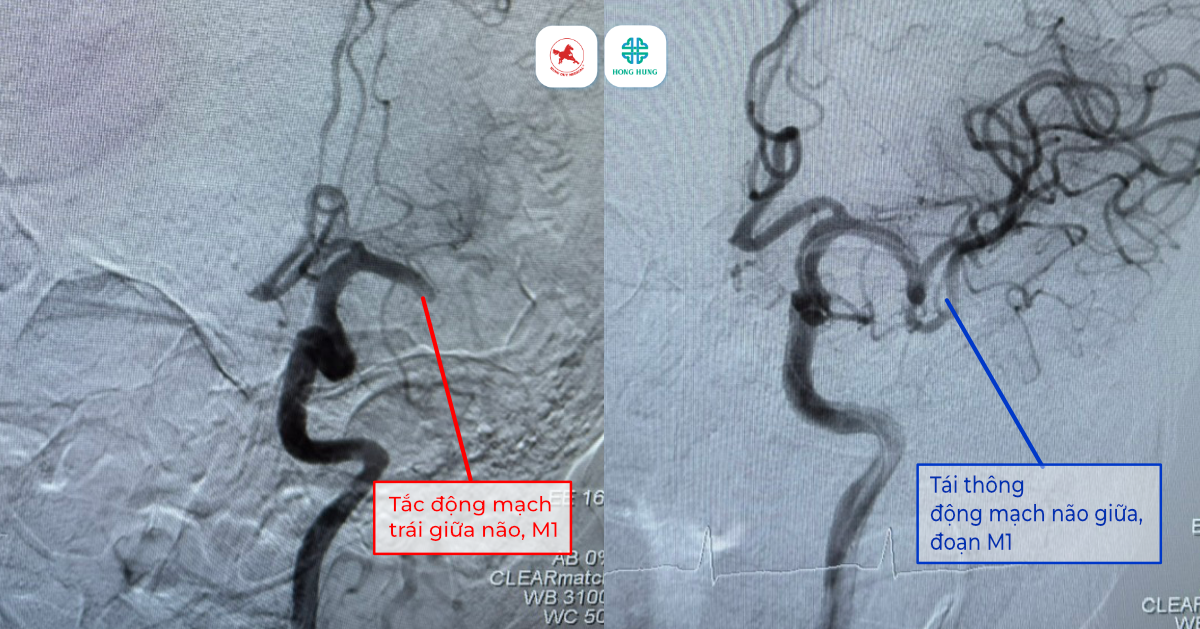

Kết quả chẩn đoán hình ảnh khẩn cấp cho thấy một kịch bản tồi tệ: bệnh nhân bị nhồi máu não cấp do tắc hoàn toàn đoạn M1 động mạch não giữa bên trái – nhánh mạch máu lớn nhất nuôi dưỡng vùng ngôn ngữ và vận động.

- Can thiệp nội mạch: Song song đó, bệnh nhân được chuyển ngay lên phòng DSA. Các bác sĩ đã thực hiện kỹ thuật hút và kéo huyết khối bằng dụng cụ cơ học để khơi thông “dòng chảy sự sống”.

Đến 01:48 sáng, sau những giây phút tập trung cao độ, nỗ lực của ekip đã được đền đáp khi mạch máu não của bệnh nhân đã chính thức được tái thông hoàn toàn.